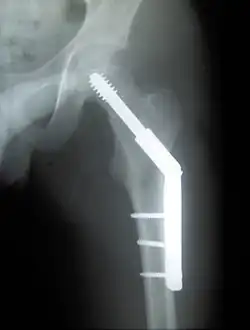

![]() | |

| Intertrochanteric hip fracture in a 17-year-old male | |